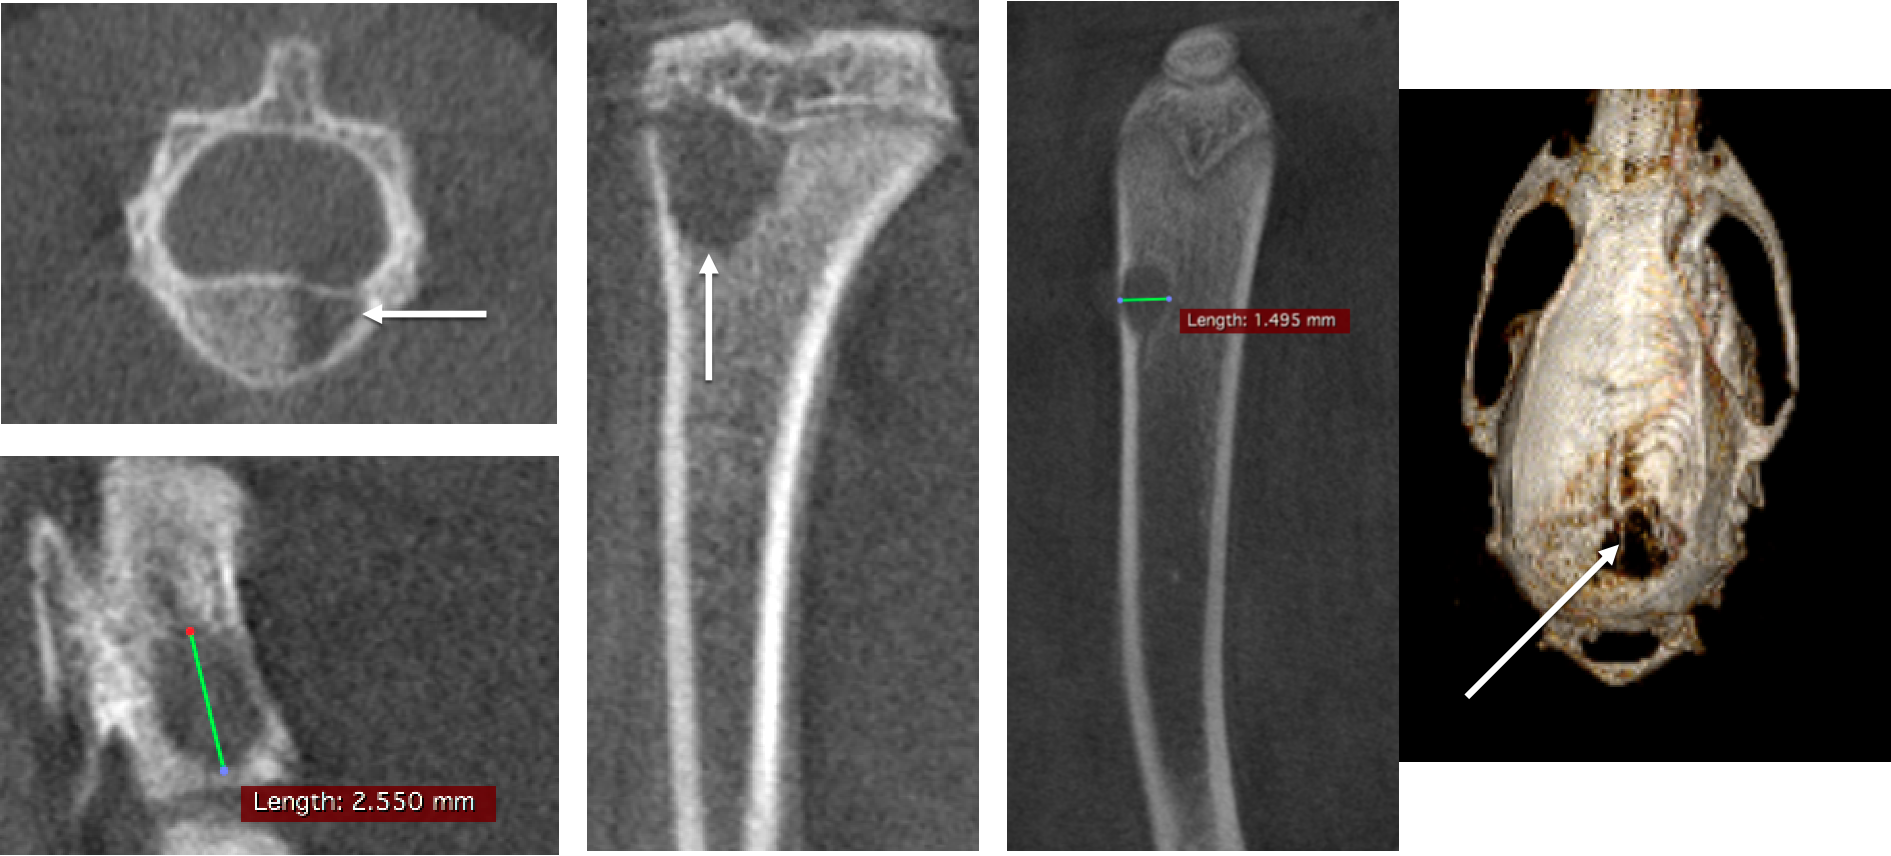

4、Bone CT imaging

Bone tumor studies: In vivo CT in rats showed that the tumor caused brain and bone metastases, a large number of cavities in the bone, FDK reconstruction, 50μm voxel size.

骨轉移.png

In vivo measurement of rat tail vertebrae: high resolution ring acquisition, acquisition time: 2min3s, ISRA reconstruction, 50μm voxel size.

尾椎骨測量.png

In vivo measurement of spinal vertebrae in rats: high definition ring acquisition, acquisition time: 4min, FDK reconstruction, 50 and 20μm voxel size.

脊椎骨測量.png